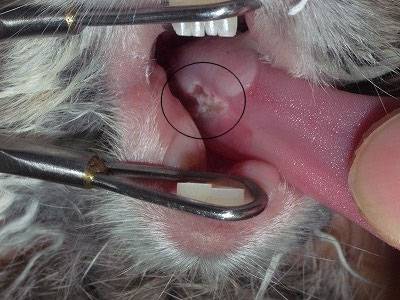

口腔内の様子。

下顎臼歯にスパイク(突起)を形成している。

出血も認める。

舌には潰瘍が認められた。スパイクが原因と思われる。